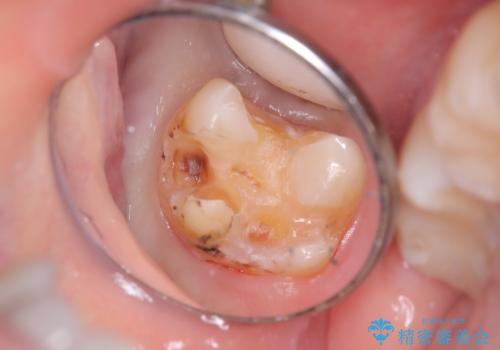

- 二次う蝕が心配という主訴で来院された患者さんです。

保険のメタルインレーは腐食しやすかったり、適合があまり良くなかったりで二次的にう蝕がインレー下で広がってしまうことが多々あります。

メタルインレーを除去したところ、残存歯質量が少なく破折のリスクを説明し、ゴールドクラウンでのやり替えとなりました。

保険のメタルインレーから二次う蝕予防(保険のメタルインレーは腐食しやすかったり、適合があまり良くなかったりで二次的にう蝕がインレー下で広がってしまうことが多々あります。)のためのやり替えだったため、材料としてセラミックとゴールドを提案したところ、展延性に優れ違和感の少ないゴールドを選択されました。